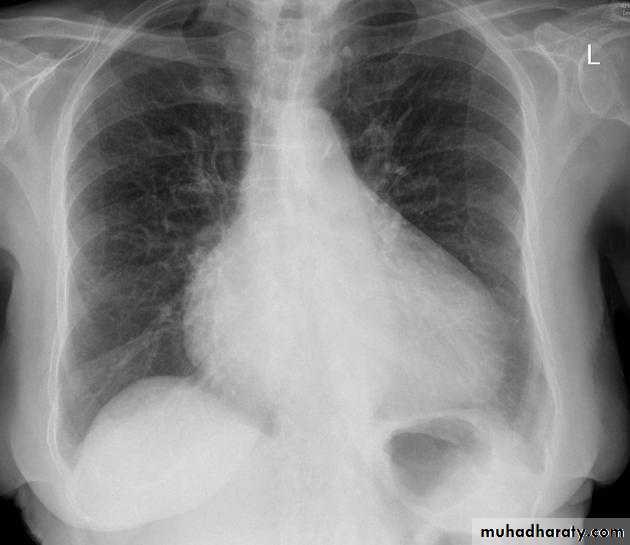

Cardiothoracic ratio (CTR) = Cardiac Width : Thoracic Width

A CTR of greater than 1:2 (50%) is considered abnormal. This however, assumes the projection is Posterior-Anterior (PA), and that cardiac size is not exaggerated by factors such as patient rotation or an incomplete breath in .

The cardiothoracic ratio aids in the detection of cardiomegaly, or more broadly, HYPERLINK "http://radiopaedia.org/articles/enlargement-of-the-cardiac-silhouette" enlargement of the cardiac silhouette.